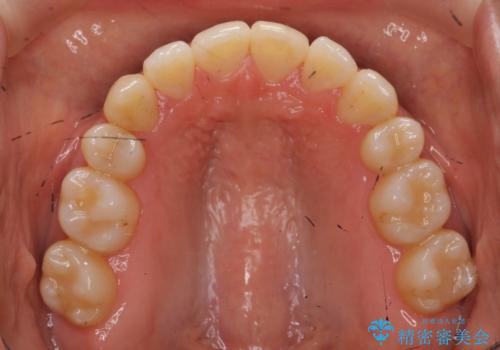

八重歯 上下の正中のずれ 40代で抜歯矯正

- 八重歯と上下の正中のずれを気にして来院。

上の前歯の正中が右にずれていました。

小臼歯抜歯を行い、ワイヤー矯正を行いました。

時間はかかりましたがしっかり治療することができました。